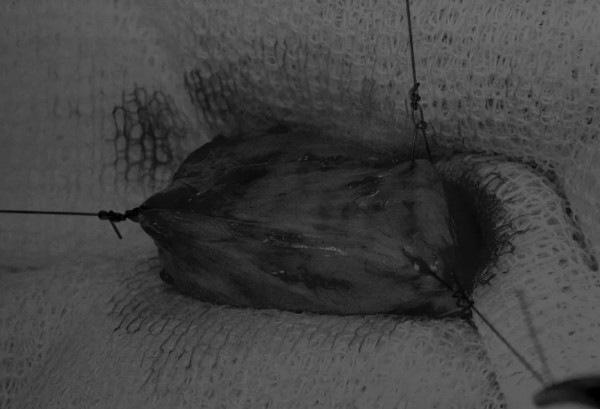

在牵引缝线之间选择血管扩张较差的区域用手术刀切开膀胱壁(图3)。在牵引缝合线之间用手术刀在血管不良的区域做切口。切开膀胱壁后,膀胱内的手术可按手术方案实施,例如取出结石(图4)。

图4 这张图显示了从膀胱中取出的大量结石